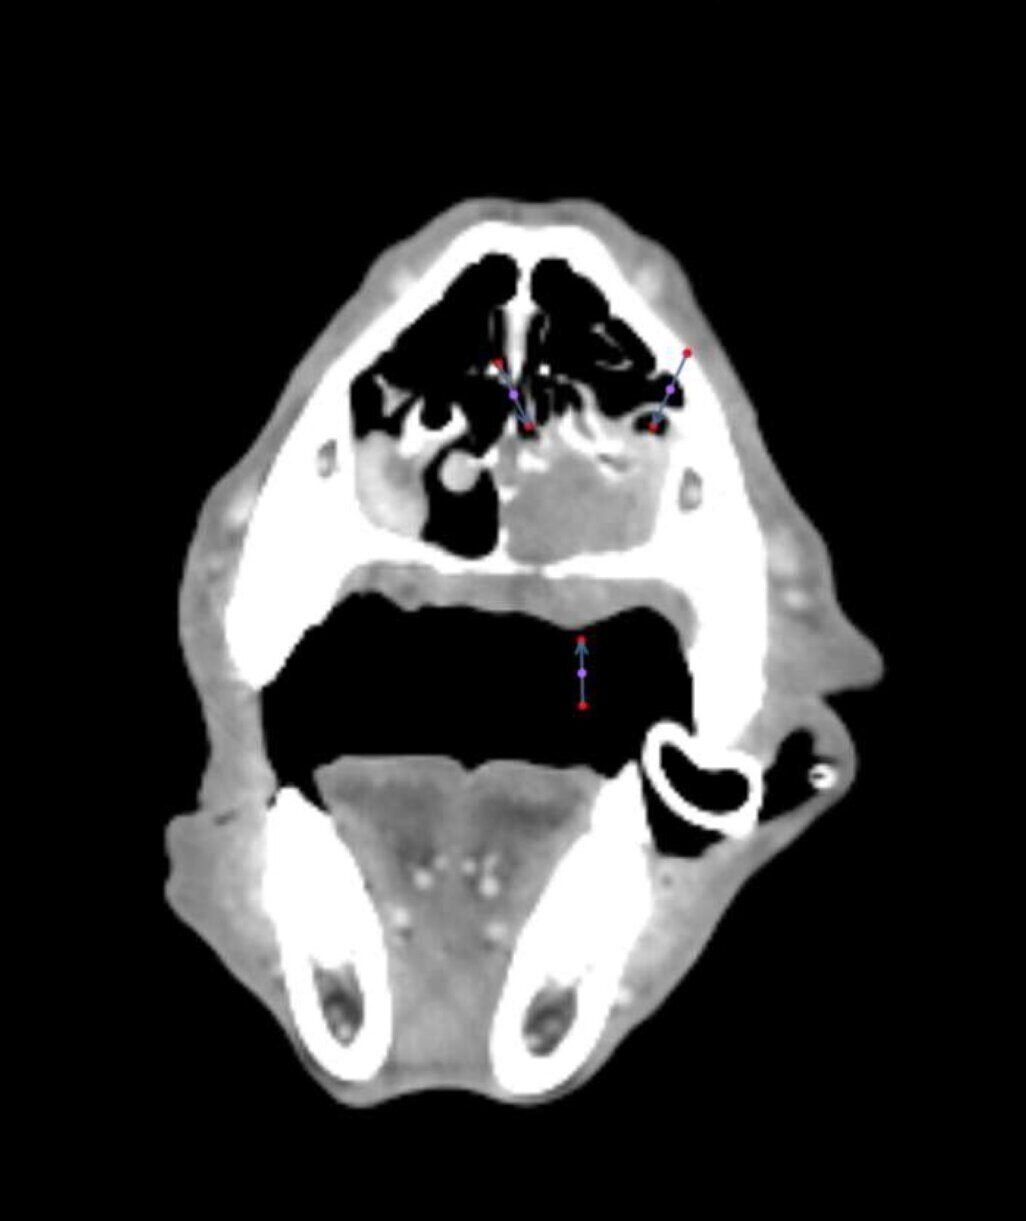

Las constantes vitales del paciente son compatibles con la normalidad. En la exploración de la cavidad oral se detecta una lesión de aproximadamente 3 cm de diámetro que se origina en la mucosa del paladar duro. No presenta linfadenomegalia submandibular o cervical palpable.

Dos semanas más tarde se realiza el TC de reestadiaje y se detecta la presencia de enfermedad metastásica en pulmón. Adicionalmente, la afectación completa del paladar y la invasión en cavidad nasal hacen que se descarte la cirugía como terapia local.

A los 18 meses del diagnóstico, los cuidadores refieren la aparición de hifema y exoftalmia en el ojo derecho, lo que sugiere metástasis, además de una masa perianal compatible con neoplasia indiferenciada (posible melanoma amelanótico). En el estudio de TC se documenta una respuesta completa de la lesión primaria y metástasis nodales y una remisión casi completa de las metástasis pulmonares (lesiones milimétricas equívocas) (imagen 1). Se realiza la resección de la masa perianal, pero los cuidadores rechazan la enucleación.